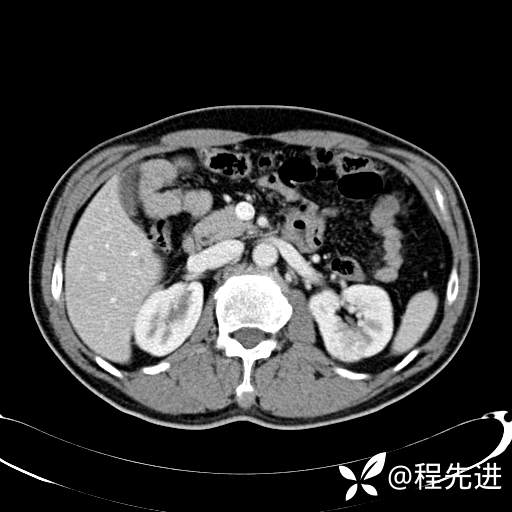

患者性别:男

患者年龄:65岁

简要病史:腰痛2月,体检发现左肾占位5天

平扫: